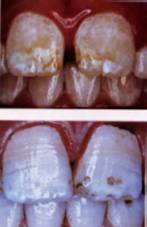

Four pictures of fluorosis (Source: Fluoride: Protected Pollutant or Panacea? Canada):

• 1st and 2nd photographs: Mild to moderate fluorosis.

• 3rd and 4th photographs: Severe fluorosis.

Five pictures of fluorosis (source: Fluoride Action Network, USA):

• Slight / moderate through to moderate-severe fluorosis..